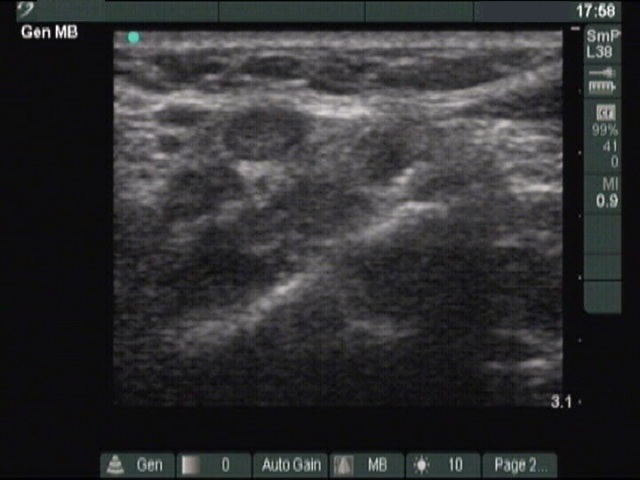

Thyroid cancers - case 185 (ultrasonographic picture 9)

Above the left lobe, transverse scan. There is an enlarged lymph node without a regular hilum.